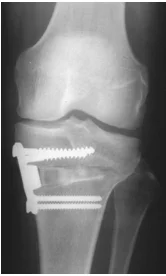

Fasciotomy Indications

- High risk patients

- Prophylactic with major corrective osteotomy of the leg & forearm

- S&S not resolved within 30-60 min. of appropriate precautions

- Significant tissue injury

- Suspicion: Equivocal clinical findings

- Based on measurements:

- Delta pressure (DBP - compartment P.) 25 mm Hg.

- Compartment pressure > 30mm Hg.